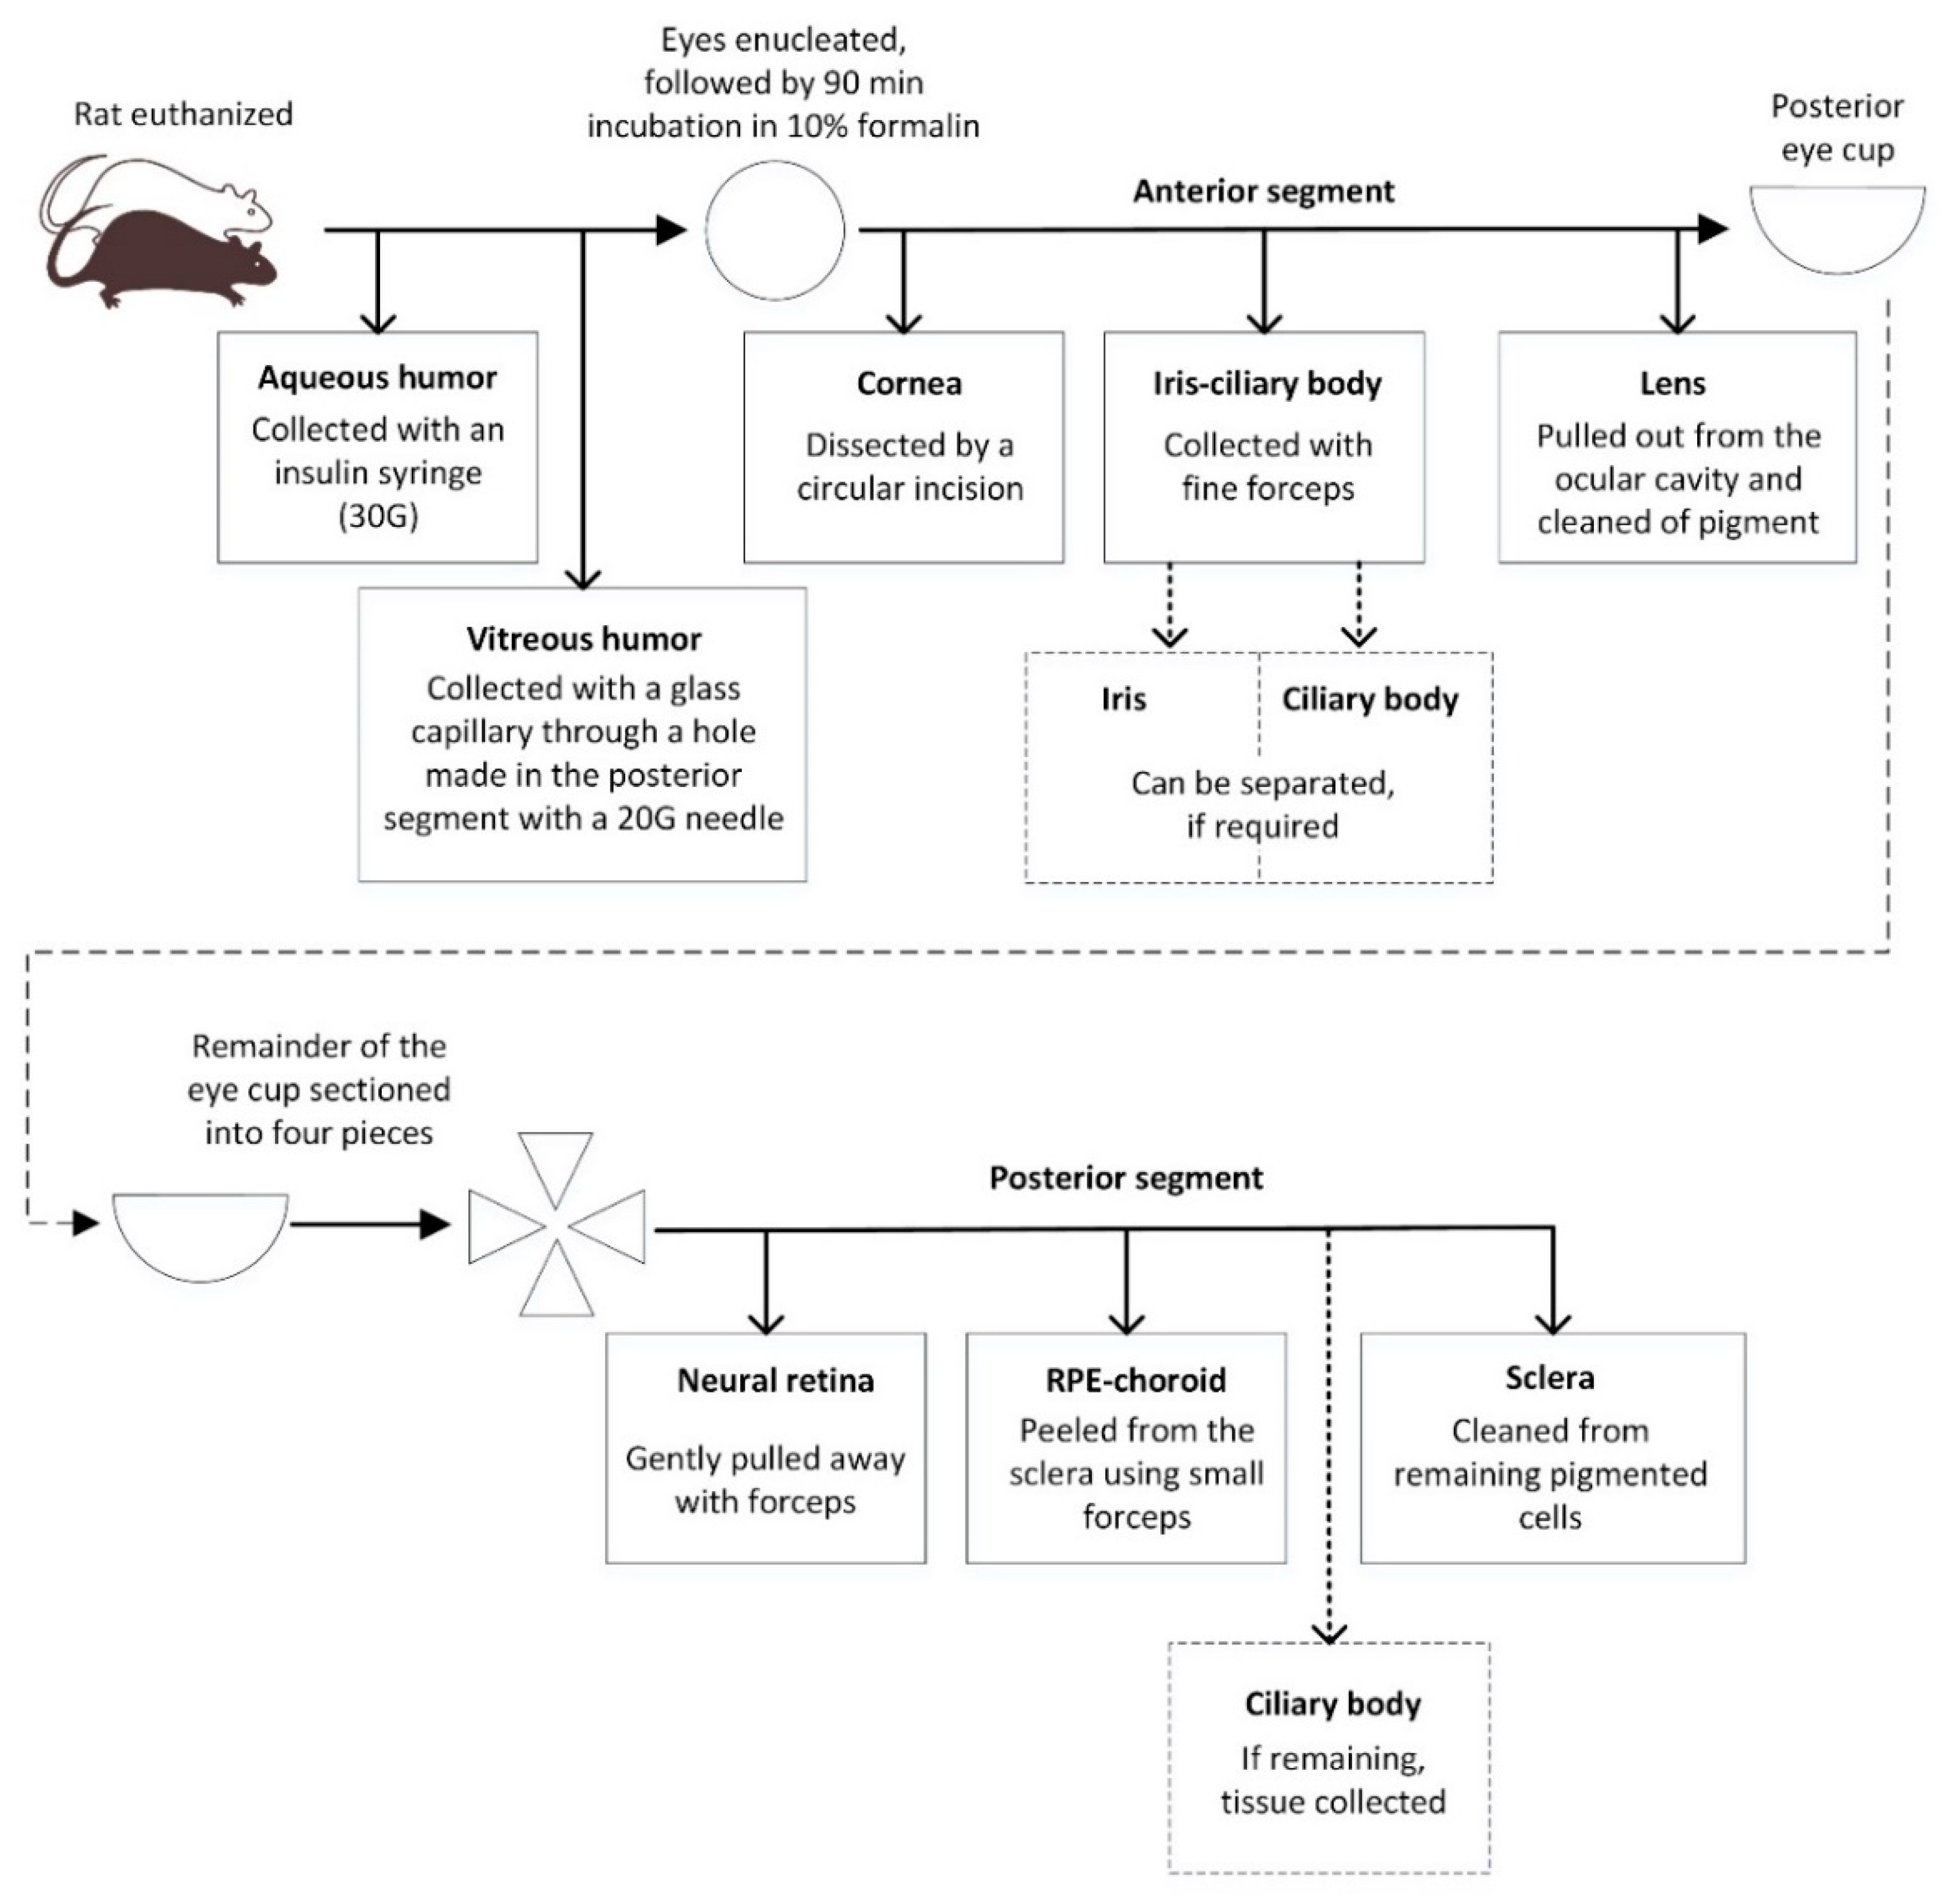

2.4. Ocular Tissue Separation and Sampling

Ocular tissue separation was performed under microscope control (Carl Zeiss f-170 Stereoscope, Oberkochen, Germany). Immediately following euthanasia, the aqueous and vitreous humor were collected. The aqueous humor was sampled via an insulin syringe (30 G) introduced through the cornea into the anterior chamber, transferred to a vial and frozen pending analysis. A sample from the vitreous humor was collected via a glass capillary using a modification of the mousetap technique [

18]. A 20 G needle was used to puncture the posterior segment of the eye (2 mm posterior to the limbus). A glass microelectrode with a broken tip (borosilicate glass, wall thickness 0.225 mm, outside diameter 1.5 mm; Hilgenberg GmbH, Malsfeld, Germany; pulled with a DMZ-Universal Puller, Zeitz-Instruments GmbH, Munich, Germany) was inserted posterior to the lens. Approximately 6 µL of vitreous humor was slowly aspirated into the glass microelectrode via silicone tubing, connected to a low volume syringe, placed in a vial and frozen.

The eye was then carefully enucleated, any extraocular material was removed, and the eye was fixed in 2 mL of 10% formalin for 90 min at room temperature. After fixation, the eye was blotted dry to remove excess formalin and placed on a holding block with the cornea facing up. Under the dissection microscope, the cornea was dissected by a circular incision in the limbus region. It was then removed and cleaned of other tissues. The iris and pieces of the ciliary body were separated from other tissues (cornea and/or lens) using a pair of fine forceps. The lens was pulled out of the ocular cavity and freed of any remaining contaminating tissue. The remainder of the eye cup was placed on a flat surface. Starting from the optic nerve toward the ora serrata, the eye was carefully sectioned into four pieces using a scalpel. If any vitreous humor was still present, it was carefully removed. Using a pair of fine forceps, the neural retina was detached from the eye at the optical nerve junction and at the ora serrata. The neural retina was gently pulled away from the eye. Heavily contaminated retinal sections were discarded and any residual pigmented tissues removed with fine forceps. The RPE-choroid was peeled from the sclera using small forceps. Care was taken not to collect the remaining part of the ciliary body that might have been left attached to the eye; the remaining ciliary body was collected and added to the iris-CB sample. The remaining scleral tissue was cleaned from adherent pigmented cells by wiping with a cotton swap. All the dissected tissues were placed in pre-weighed tubes. All tubes were weighed and the tissue weights recorded. The step-by-step tissue separation process is described in

Scheme 1 and illustrated in

Figure S1.

23], they rarely report the methods by which the different ocular tissues were isolated and treated after the isolation. In particular, for species with smaller eyes (rat eye diameter ca. 6 mm), the availability of robust, reproducible separation methods is an important cornerstone to gain better understanding of ocular drug distribution and PK/PD. We describe, here, a method allowing a stepwise separation of the anterior and posterior substructures of the rat eye and quantification of small molecules in the separated structures. The reported method, based on a short fixation of the eye in formalin before tissue separation, offers a simple and refined way to isolate the specific tissues with minimal cross-contamination.

Small molecules exhibit high melanin binding potential, stressing the need for clean separation of the posterior segment tissues, retina and RPE-choroid, since a small contamination of the retina with melanin containing tissue could lead to a considerable over-estimation of retinal drug concentrations. Unfortunately, retina and RPE-choroid of the rat eye are very difficult to distinctly separate from one another. We chose to fix the eye in formalin before the separation process, as formalin is known to induce retinal detachment [

24] and preserve tissue structure. A short fixation time of 90 min, considerably shorter than the generally used tissue fixation times for histology purposes (overnight or longer), was optimal for our purpose.